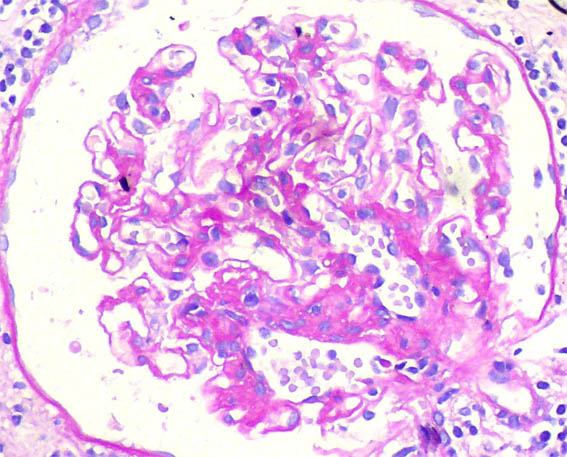

Figure 1. H&E, X400.